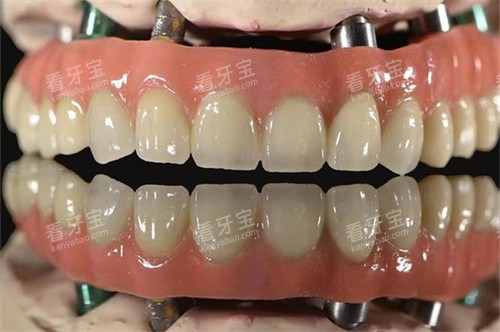

全口吸附性义齿是一种采用特殊设计的修复体,通过功能性印模技术和边缘封闭系统,在口腔内形成稳定的负压吸附力,使假牙能够紧密贴合牙槽骨黏膜表面。与传统活动假牙相比,它的稳固性和舒适度都有显著提升,外观也更接近自然牙齿。

采用德国进口BPS生物功能性材料的吸附性义齿,能良好模拟天然牙咬合力,生物相容性好,吸附力强,适合对舒适度和功能性要求较高的用户。

采用德国生物吸附技术,啃咬功能接近真牙,特别适合牙槽骨重度萎缩的老年患者。